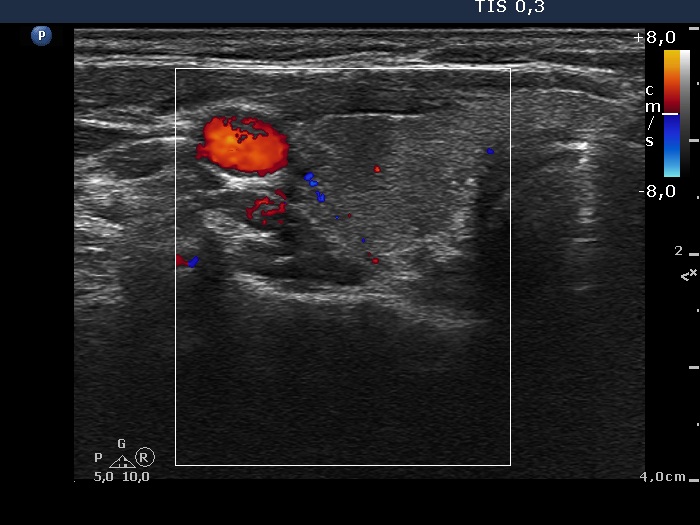

Follow-up 5 years later (3rd row of images):

Clinical presentation: Six months after the previous visit the patient became pregnant. The TSH was 5.91 mIU/L at the 5th gestational weeks. Replacement therapy was given which was ceased after delivery. The patient was free of complaints and the TSH was in the normal range, even during a next pregnancy 2 years later. Recently, a few weeks after COVID-19 infection, she noticed tenderness in the right side of the neck.

Palpation: no abnormality.

Laboratory tests: TSH 1.72 mIU/L, CRP 3.5 mg/L.

Ultrasonography: The thyroid was intact.

1. This is one of the characteristic courses of subacute thyroiditis.

2. We always suggest TSH evaluation if the patient becomes pregnant within 5 years after a granulomatous, subacute thyroiditis.

3. A discrete hypoechoic lesion of thyroiditis frequently resembles a suspicious nodule with blurred and lobulated margins and nonparallel orientation, as happened in this case. We must be aware of the clinical data when analyzing an ultrasound pattern.